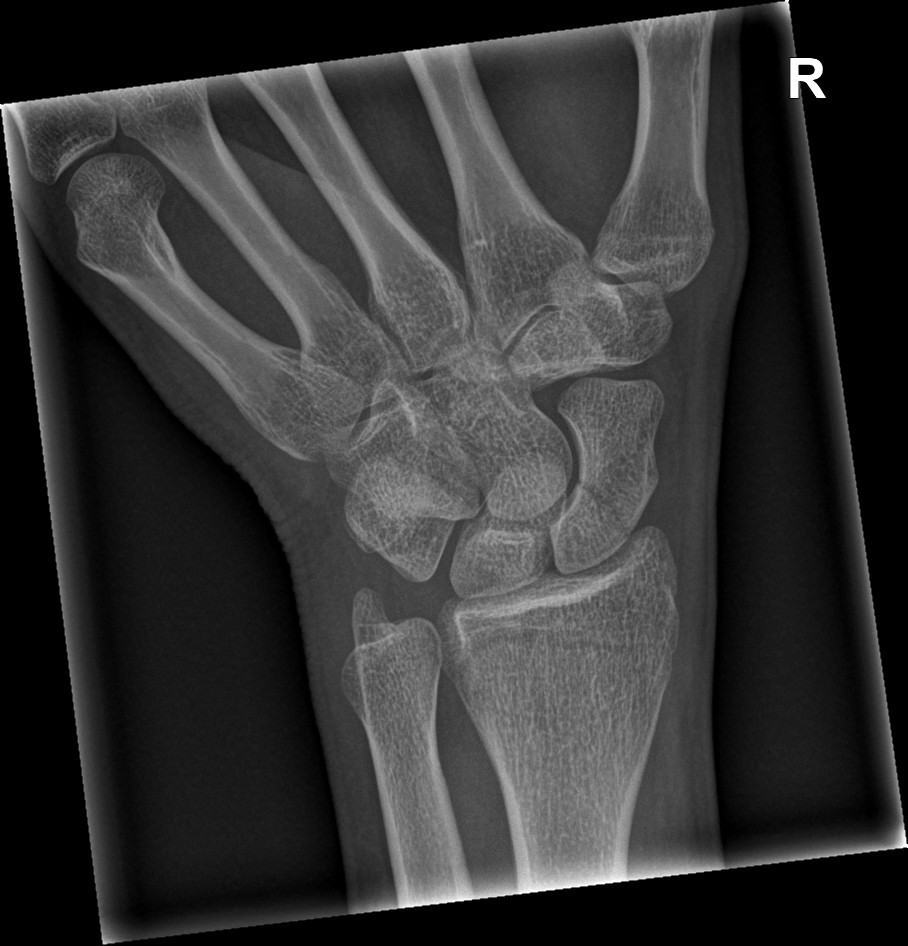

Aanvullend onderzoek: Bij vermoeden van een scaphoidfractuur wordt een gerichte röntgenfoto van het polsgewricht gemaakt in specifieke standen om het scaphoid goed te kunnen zien. Vaak blijken kleine scheurtjes of breuken al zichtbaar. Toch kan het gebeuren dat de eerste foto geen afwijking toont, terwijl er wel degelijk een barst in het scaphoid zit. Daarom is het protocol dat, als de pijn blijft, na 10-14 dagen opnieuw röntgenfoto’s gemaakt worden, of meteen een CT-scan om de breuk alsnog aan te tonen. Soms wordt een CT-scan gebruikt om de exacte positie van de breuk en eventuele verplaatsing beter in beeld te brengen, vooral in het kader van operatieve planning.